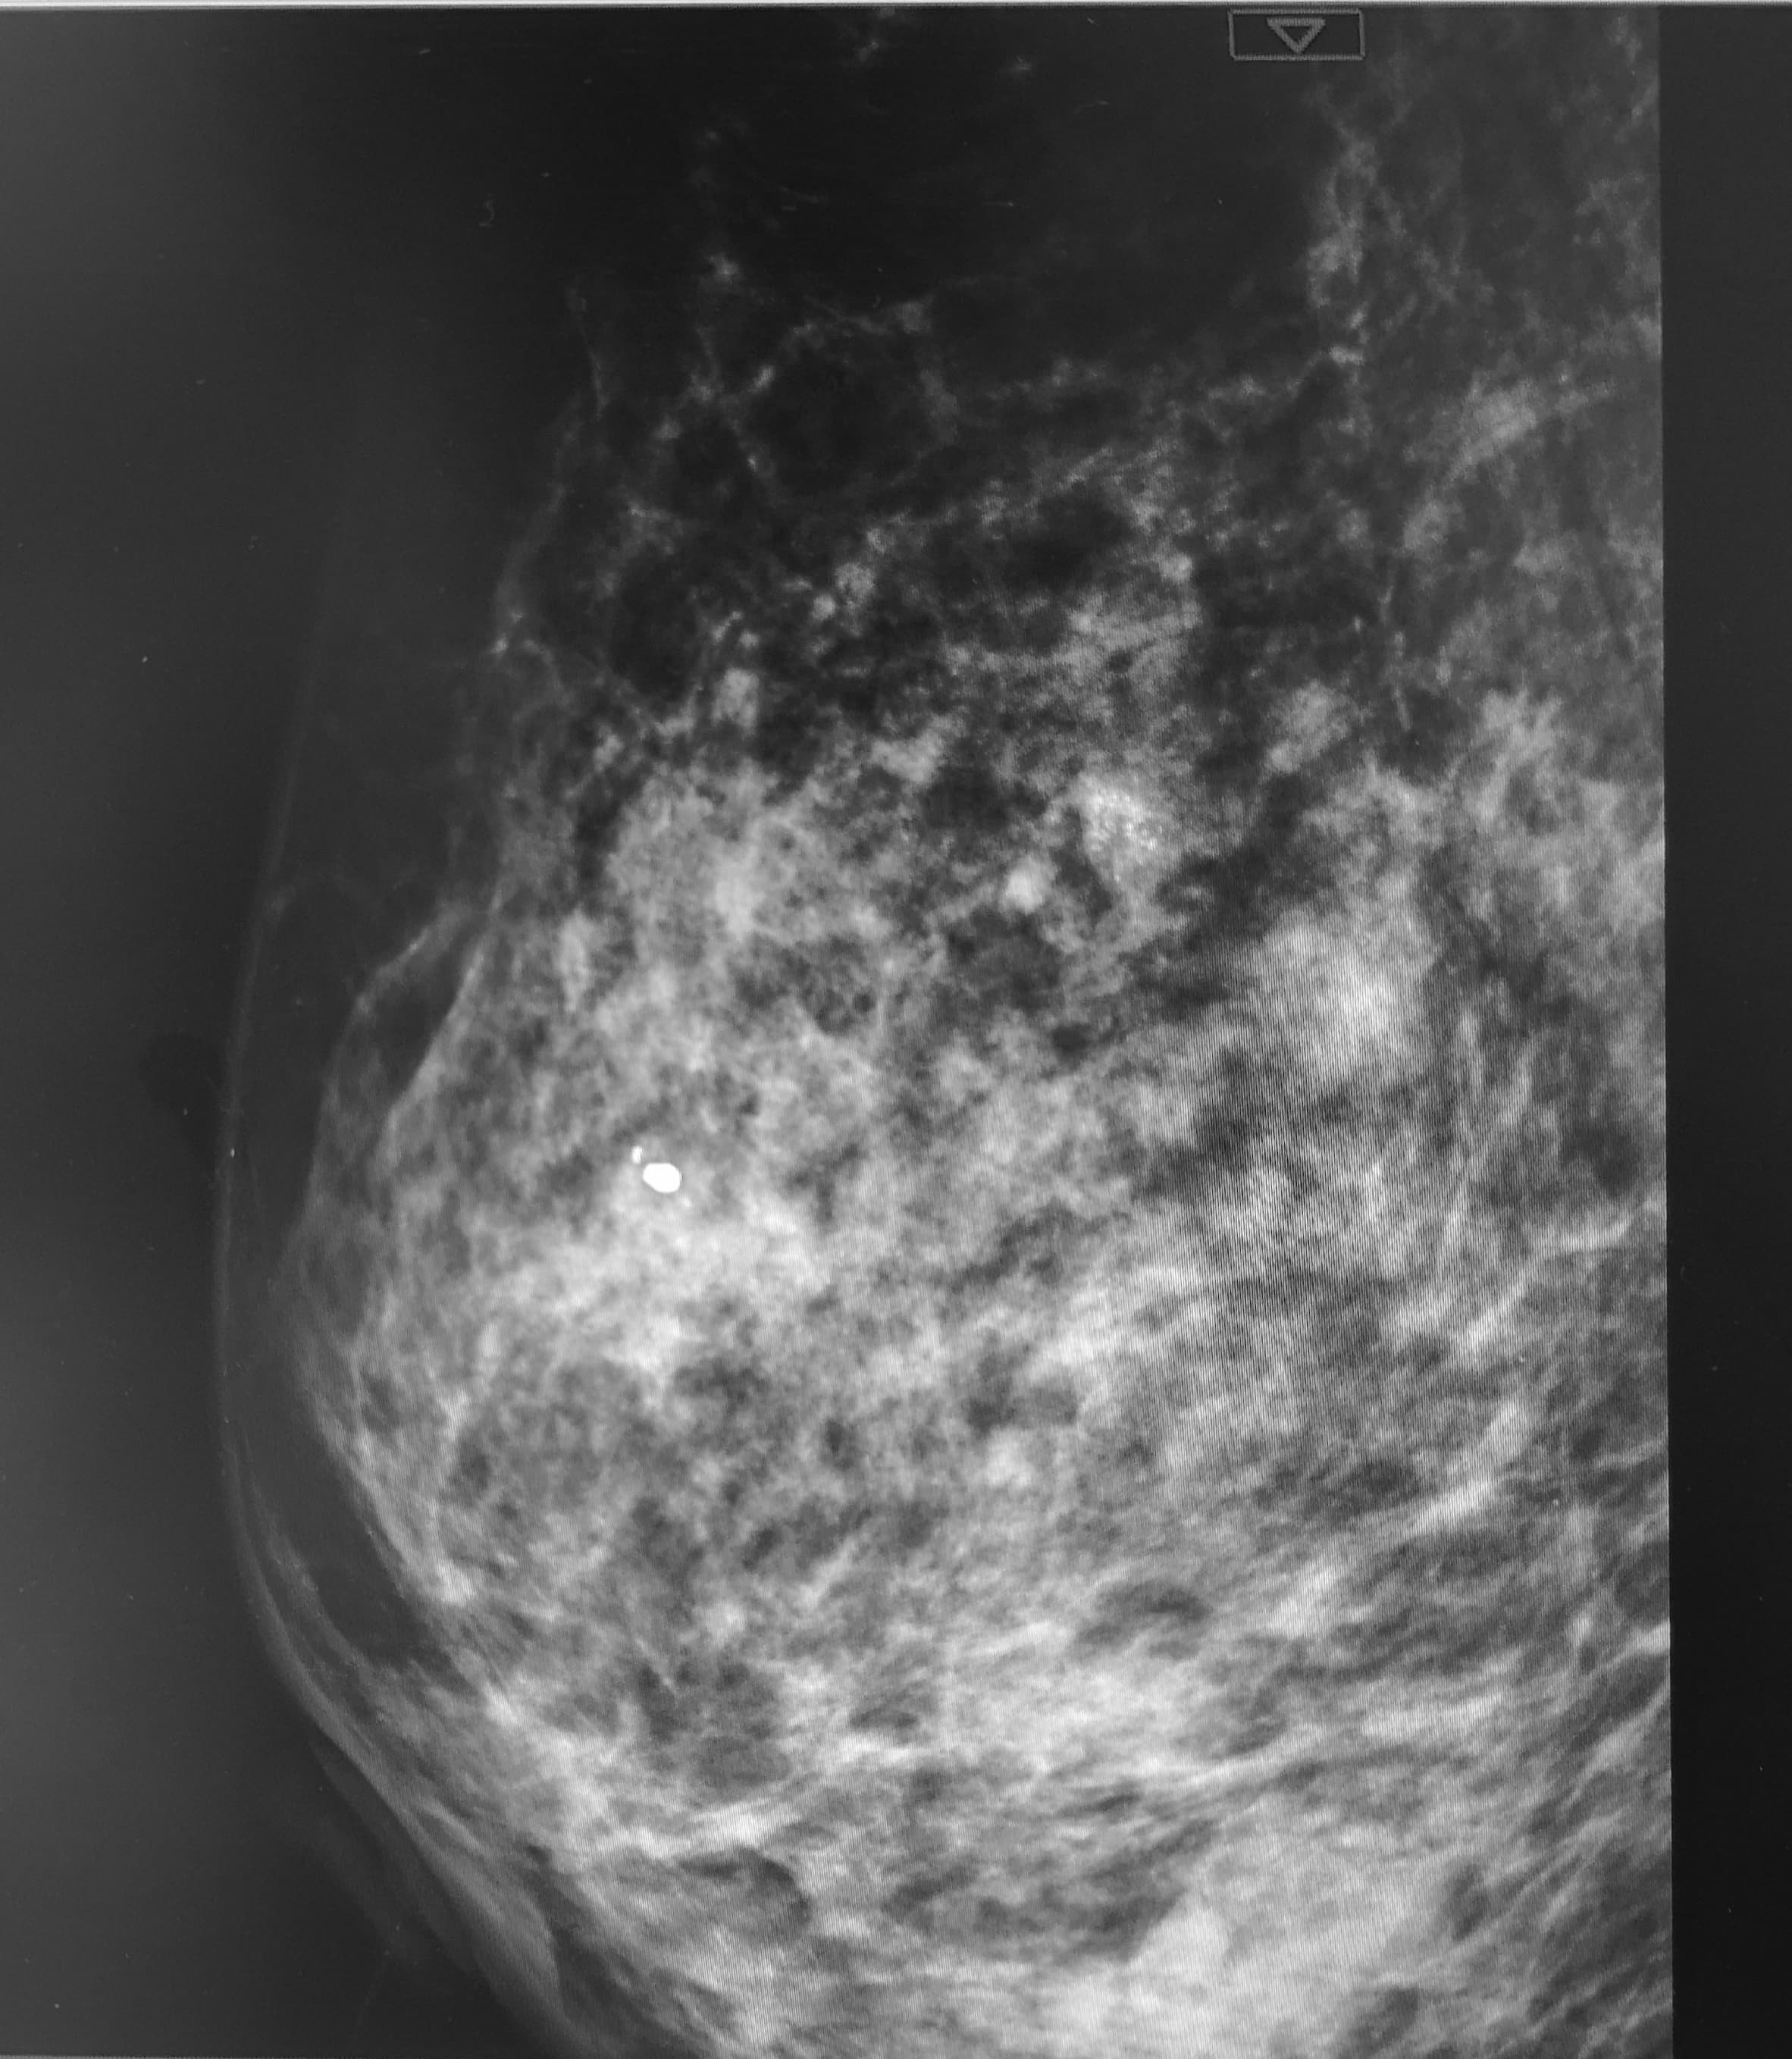

乳房钙化点一旦产生是不可能治愈的,因为钙化点本身不是疾病,也不可能消失以下是关于乳房钙化点的详细解释钙化点的本质钙化只是在组织内发生的一种现象,可能是由于局部细胞的一些点状坏死,或导管内的一些钙盐类沉积物造成也有一部分人是由于乳腺肿块内发生了多发的坏死而产生钙化点钙化点的特性;乳房有钙化点的治疗需根据钙化点性质患者年龄及生理状态综合制定方案,具体如下一钙化点评估与诊断首先需通过乳腺超声钼靶等检查明确钙化点特征,包括大小形态如沙粒样或粗大分布密集或散在等沙粒样密集分布的微钙化点恶性风险较高,而粗大散在的钙化点多为良性年龄因素影响。

乳房钙化是超声表现,是钙质沉积导致,良性恶性疾病都会出现钙质沉积,应加以区分患者出现乳房不适时到医院检查,一旦确诊有钙化灶就认为是恶性肿瘤其实钙化灶大小不同,而且也有良性恶性区分钙化灶主要就是由于结核炎症引起,局部组织中钙盐沉积就会形成钙化灶检查是良性的钙化,说明以前曾有过;此类钙化点多为乳腺组织退行性改变或既往炎症愈合后遗留,不影响健康,也无需“治愈”2 可能提示乳腺癌的钙化点需进一步检查若钙化点呈现簇状细小多形性分支状等可疑特征,可能提示乳腺癌前病变或早期癌变此时需通过活检如穿刺活检真空辅助活检明确病理性质若确诊为乳腺癌,治疗需根据肿瘤。